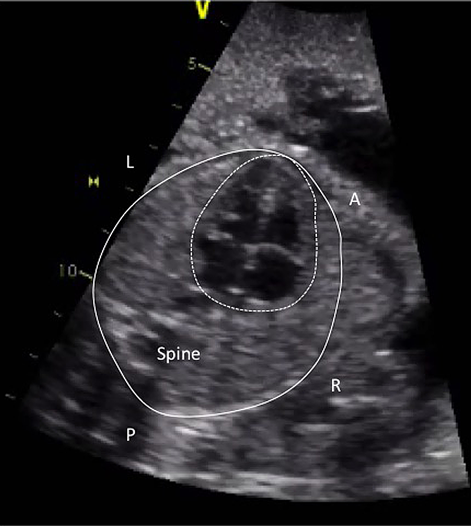

いわゆるレントゲンの心胸郭比に相当する,グローバルな心機能の指標である.計測には総心横径(total cardiac dimension: TCD)と心胸郭面積比(cardiothoracic area ratio: CTAR)がある.TCDは四腔断面において,三尖弁付着部の心外膜から僧房弁付着部の心外膜までを測定したもので,22週以降では数週mmが正常値とされている.CTARは四腔断面で心膜外側をトレースした心臓の面積を脊柱や肋骨を含み,皮膚や筋肉を含まない胸郭の面積で除して求められる (Fig. 1).簡便のため両方を楕円で近似したellipse法が多く用いられる.正常は0.20~0.35.

Fig. 1 Measurement of the cardiothoracic area ratio

A four-chamber view of the fetal heart. The thoracic area is indicated by a solid line, and the cardiac area was by a dotted line. (A: anterior, L: left, R: right, P: posterior)